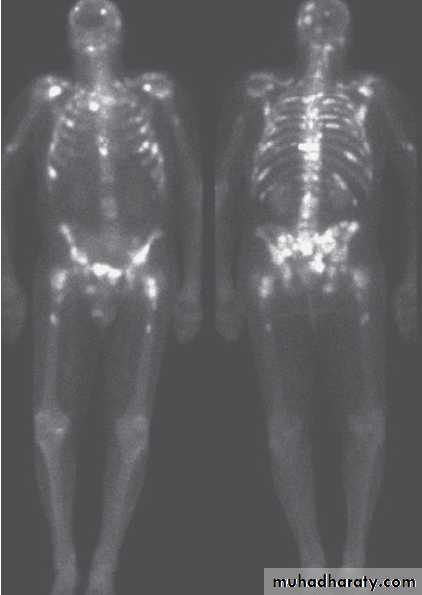

Bone pain due to metastasis to bone( osteoblastic lesions).

3. Axial imaging (CT, MRI).4. Bone scan.